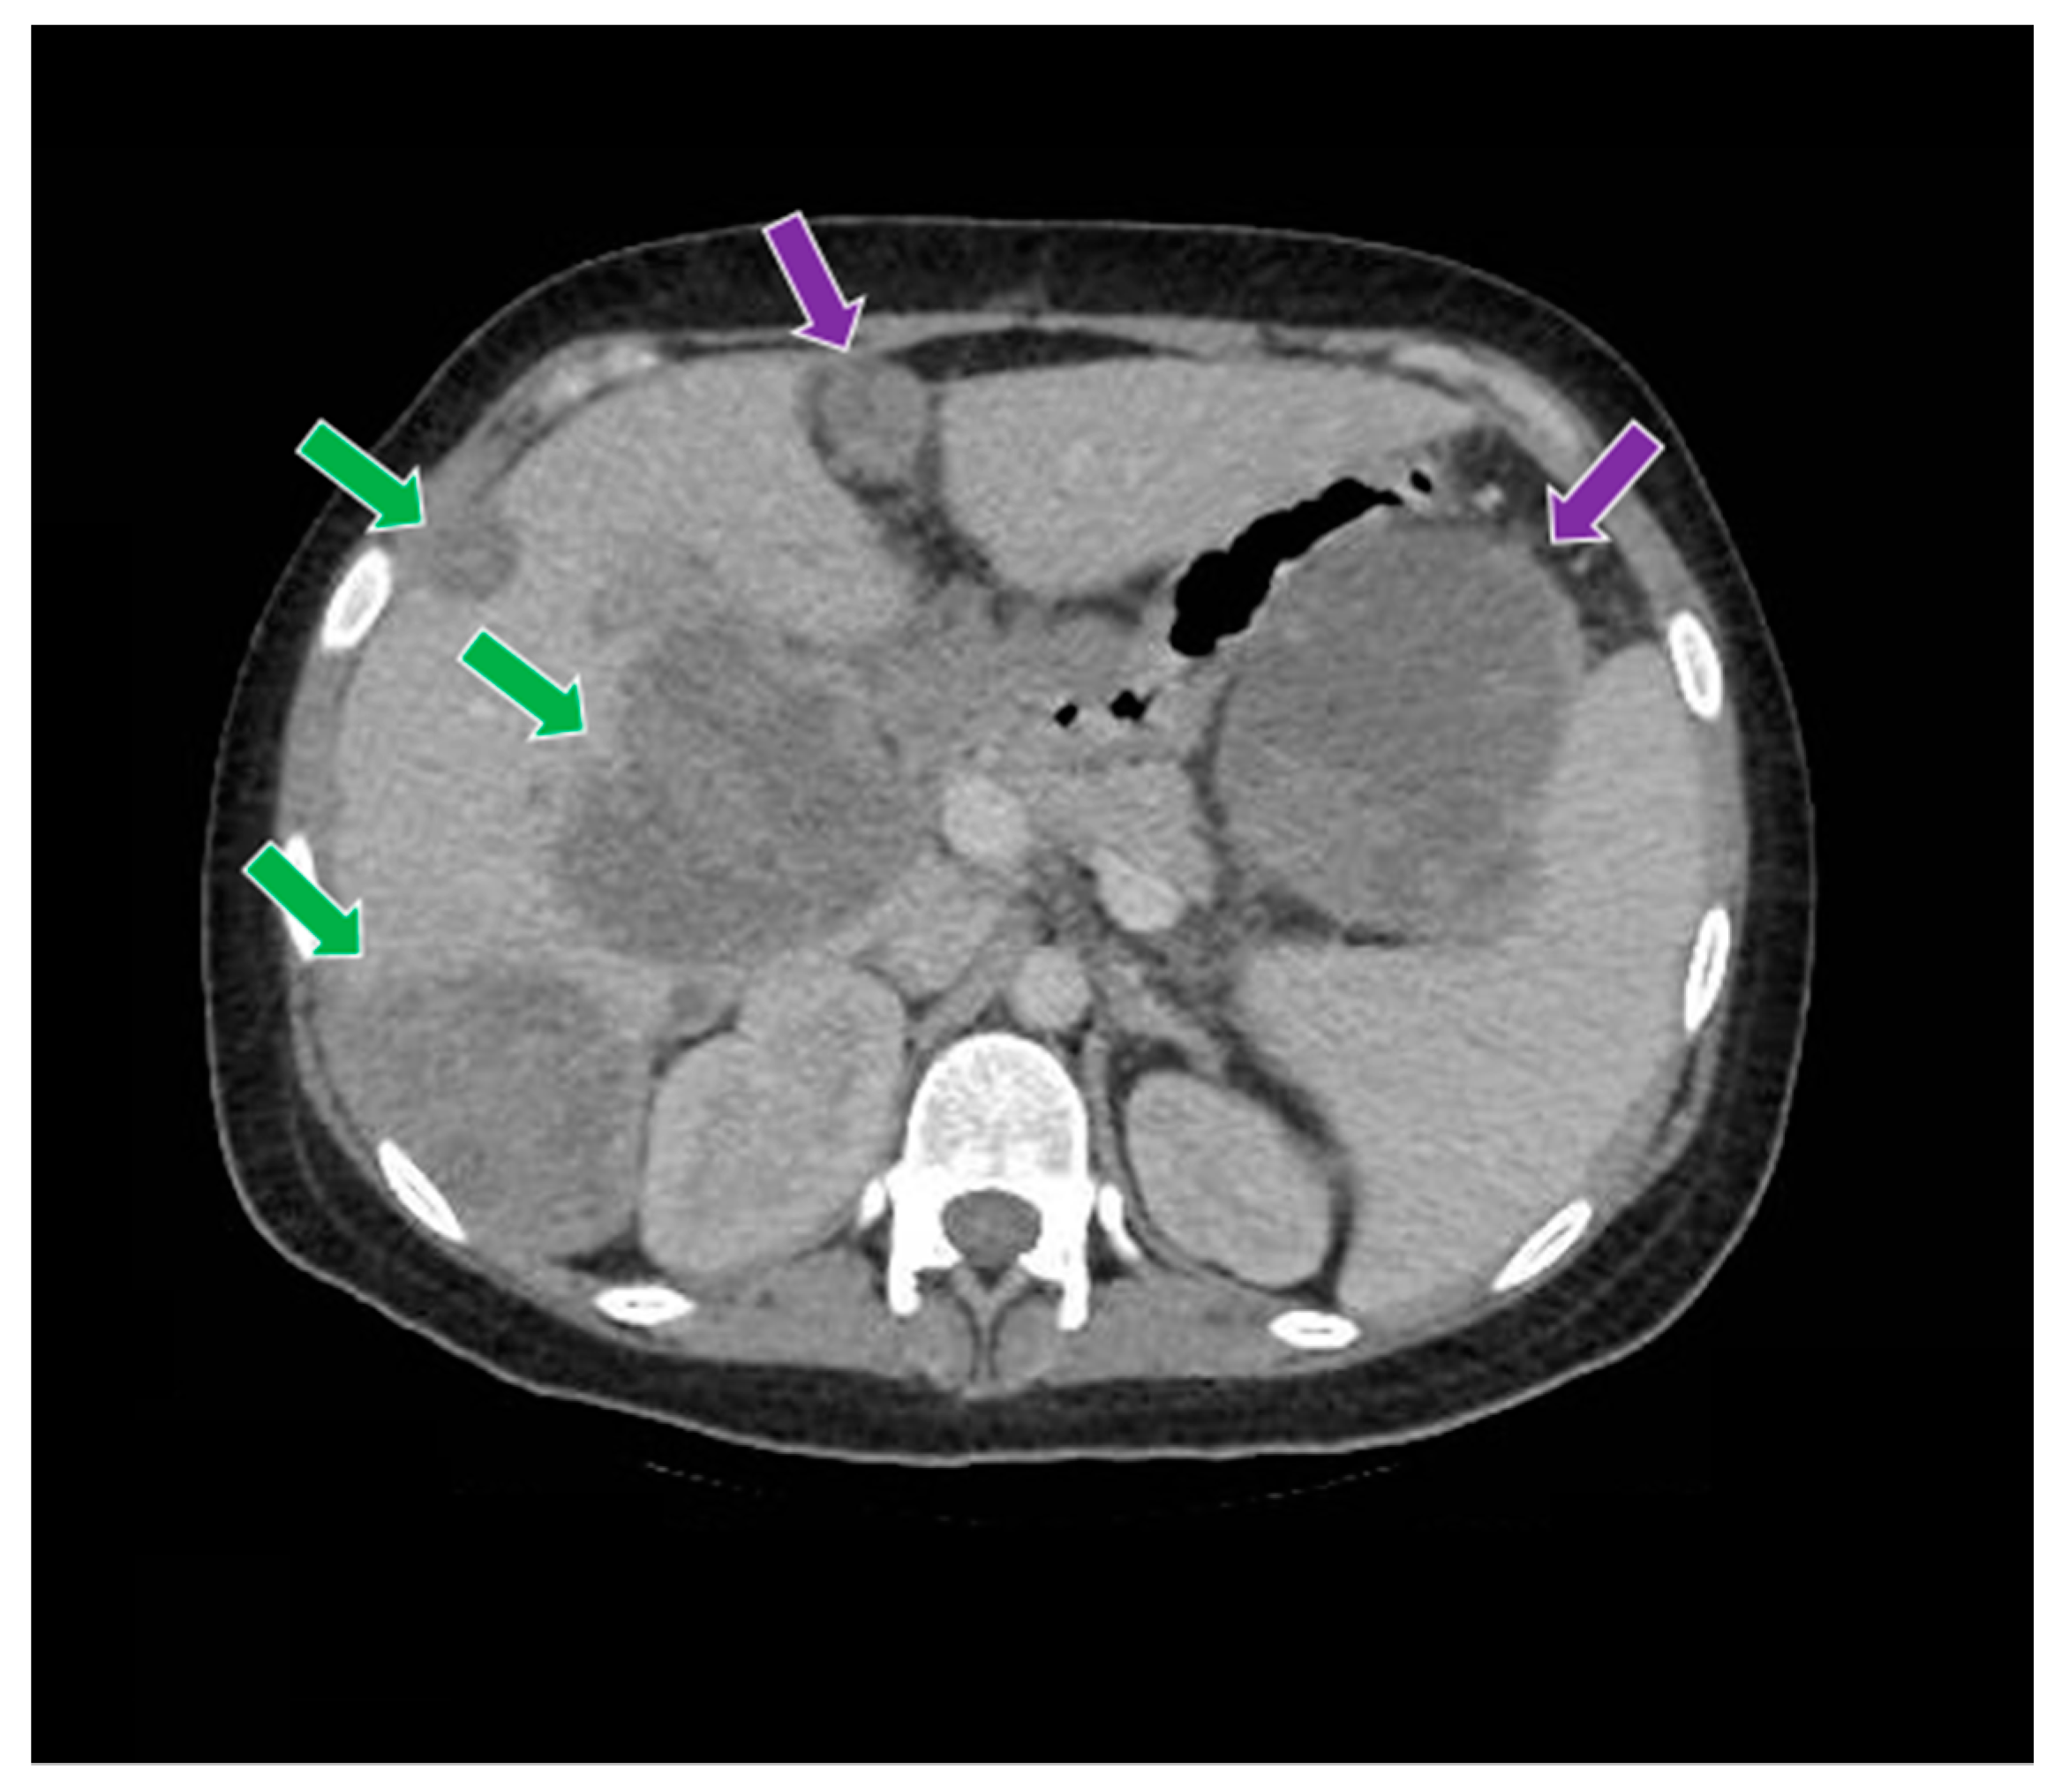

Figure 9.

The computed tomography study in the portal phase demonstrates liver metastases (green arrows) and abdominal metastases (purple arrows).